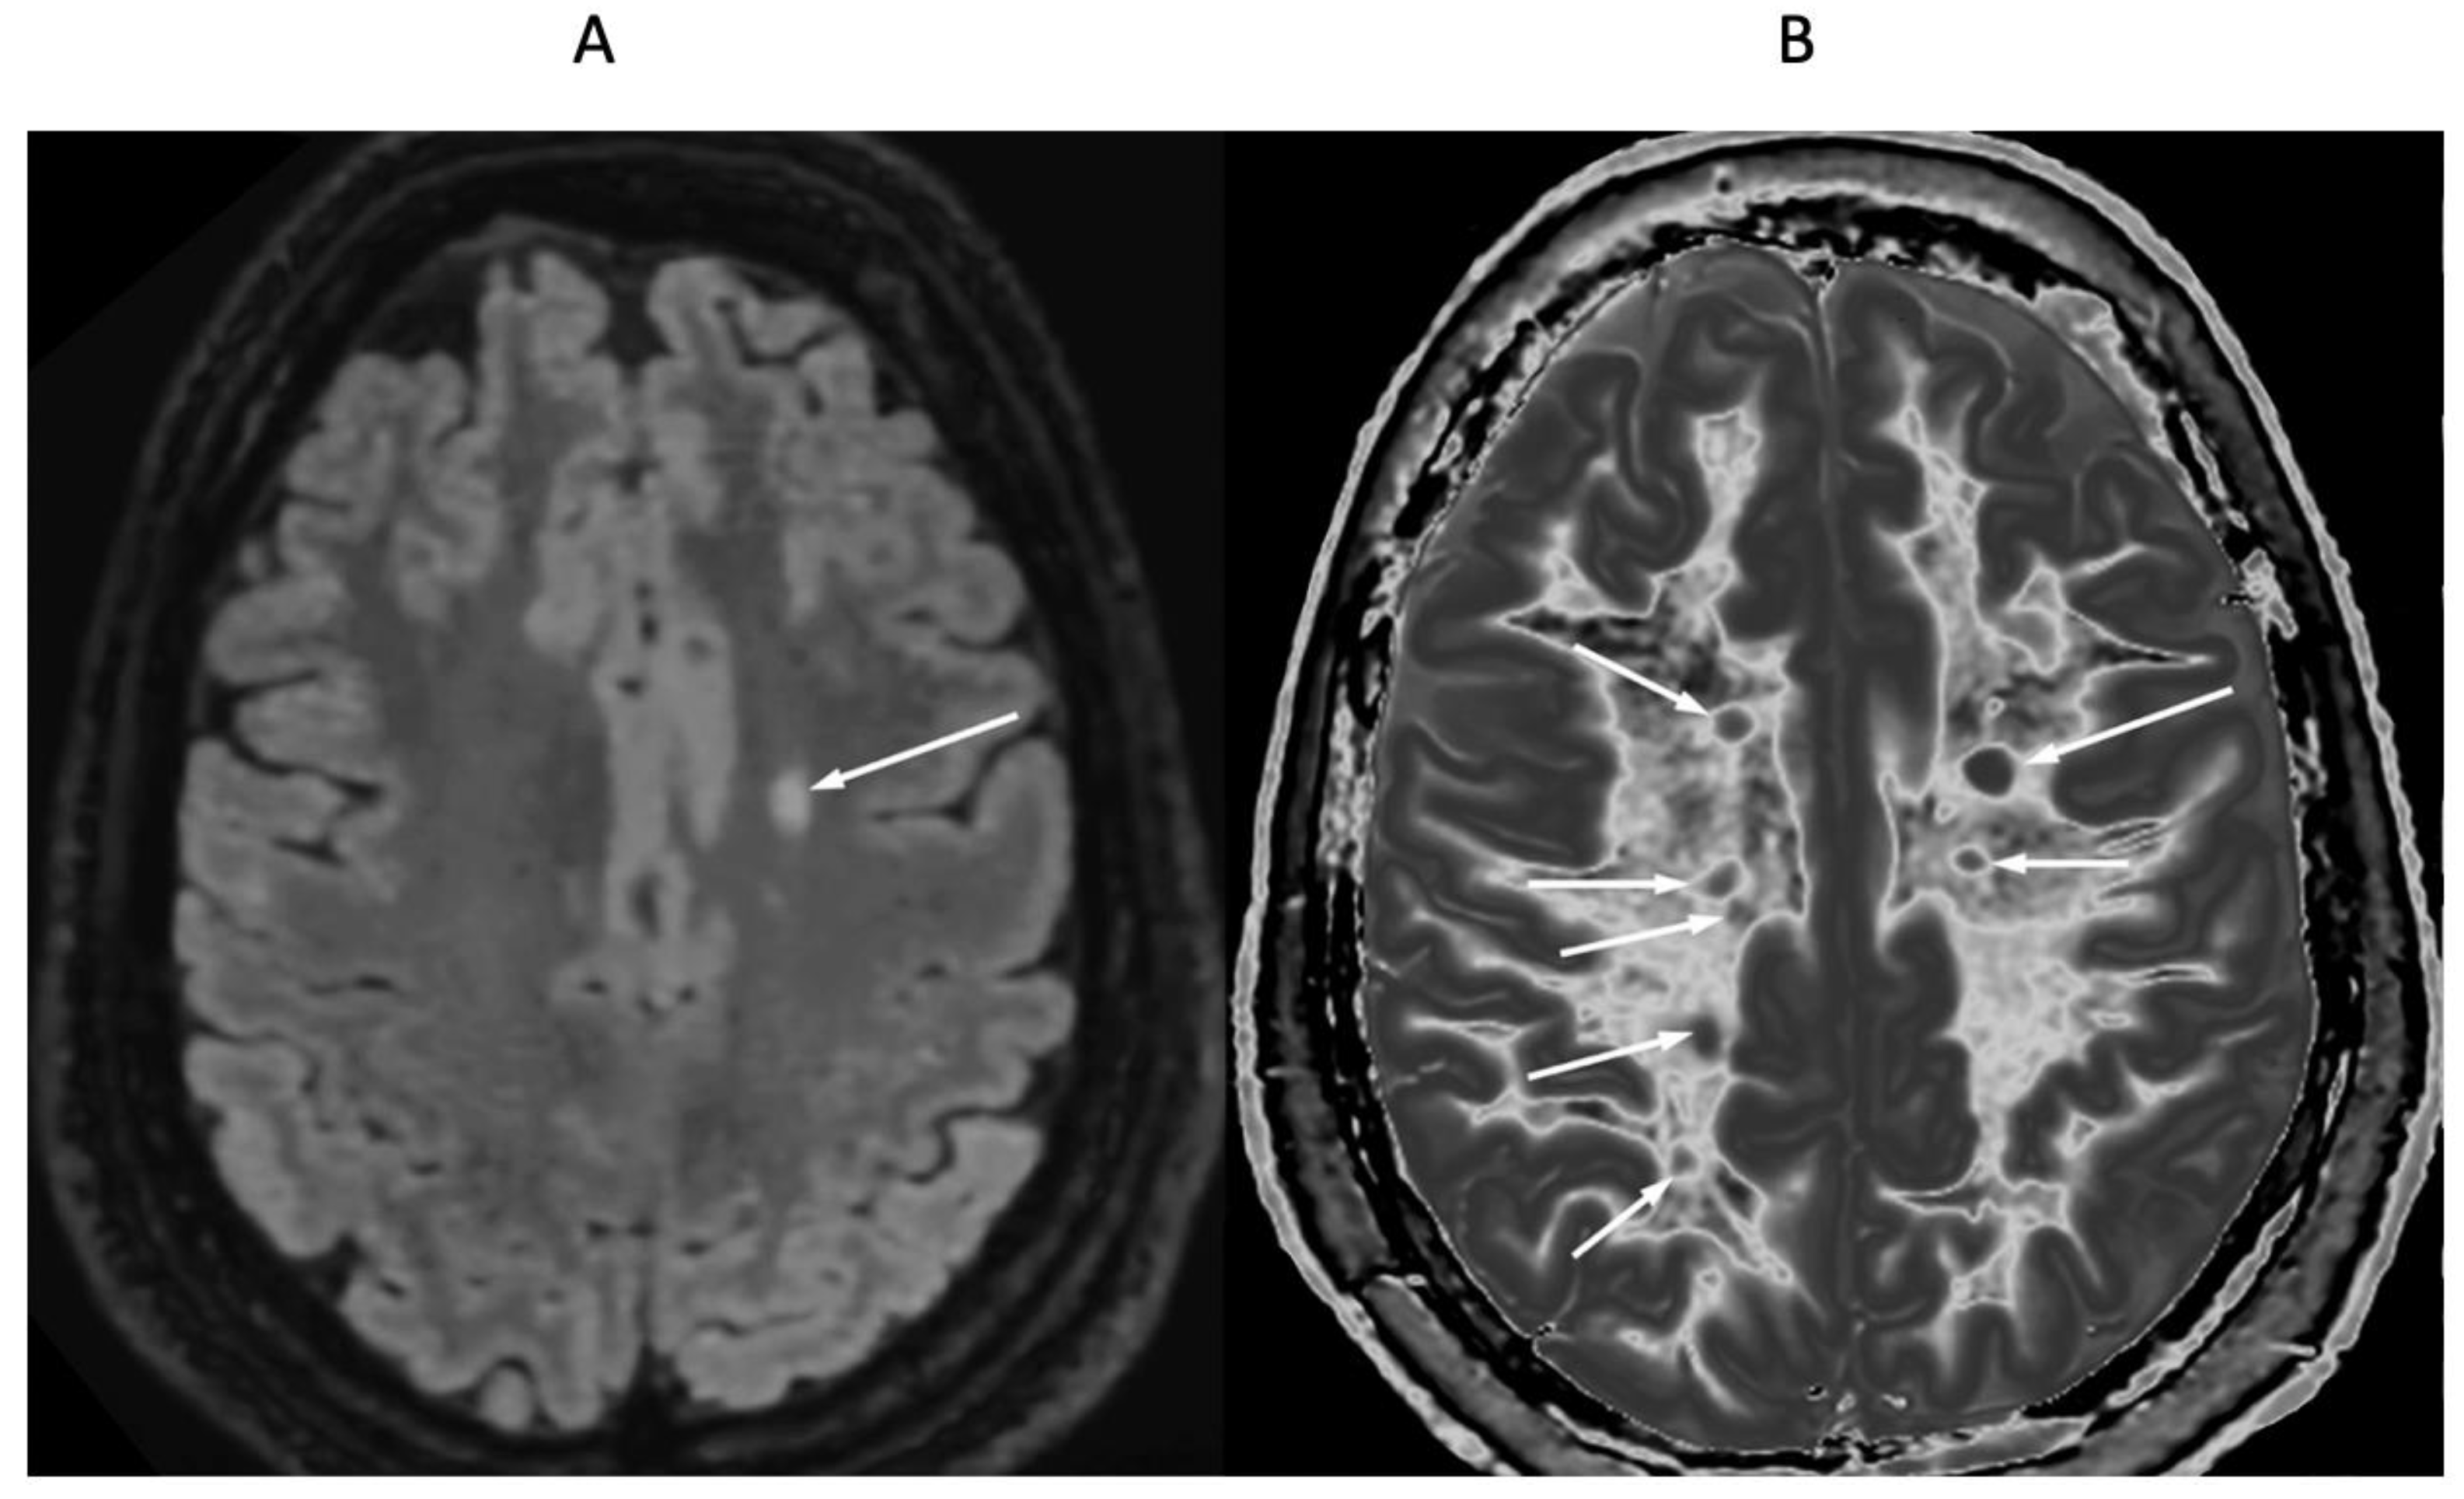

4. Illustrative Cases

5.2.1. Whiteout Sign

5.2.2. Grayout Signs

5.3.1. Activity